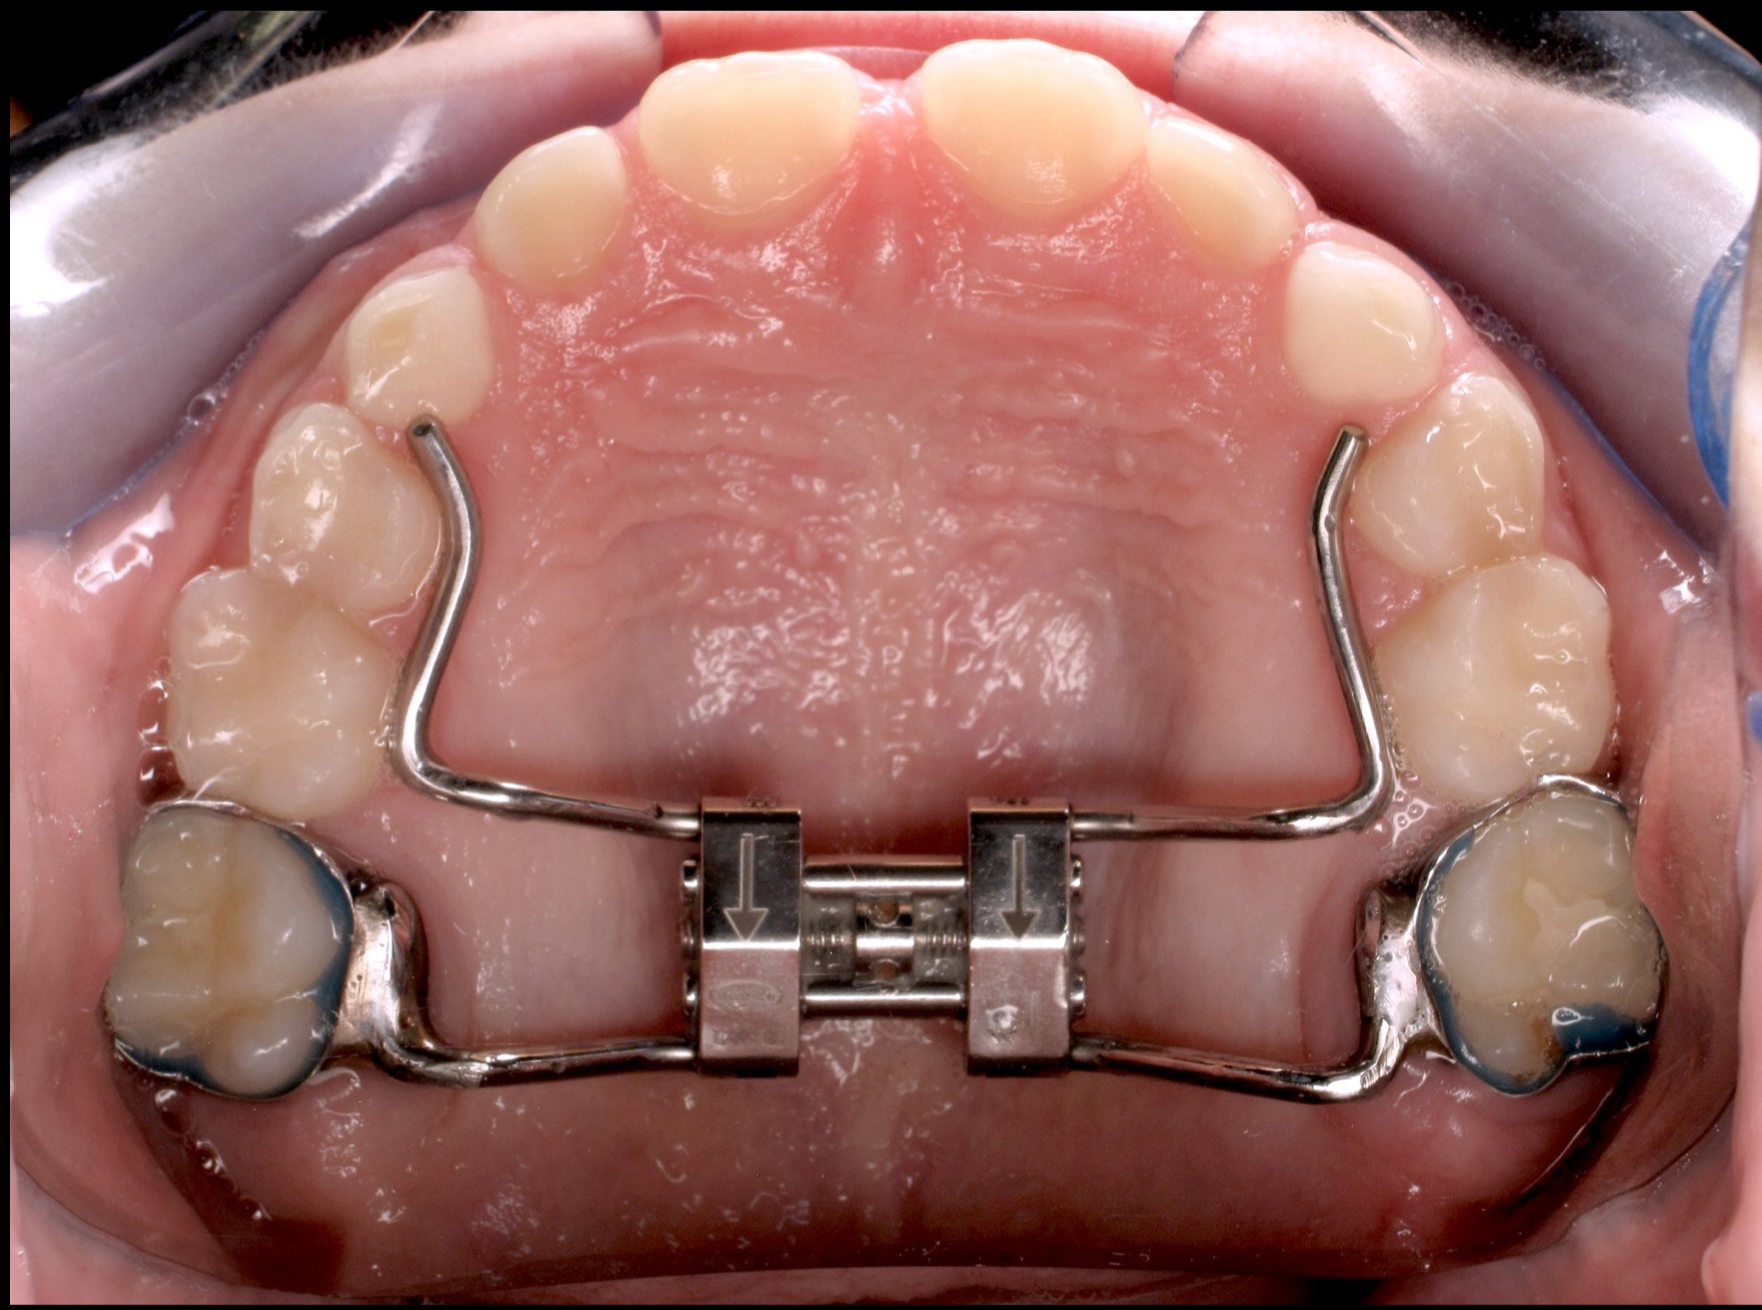

Other types of orthodontic appliances may also be used during the course of treatment. Some of these appliances are removable and can be taken in and out of the mouth, while others will be attached to the teeth until they are no longer needed.

- Widening the jaws to make sufficient space for permanent teeth

- Allowing the correction of teeth in crossbite